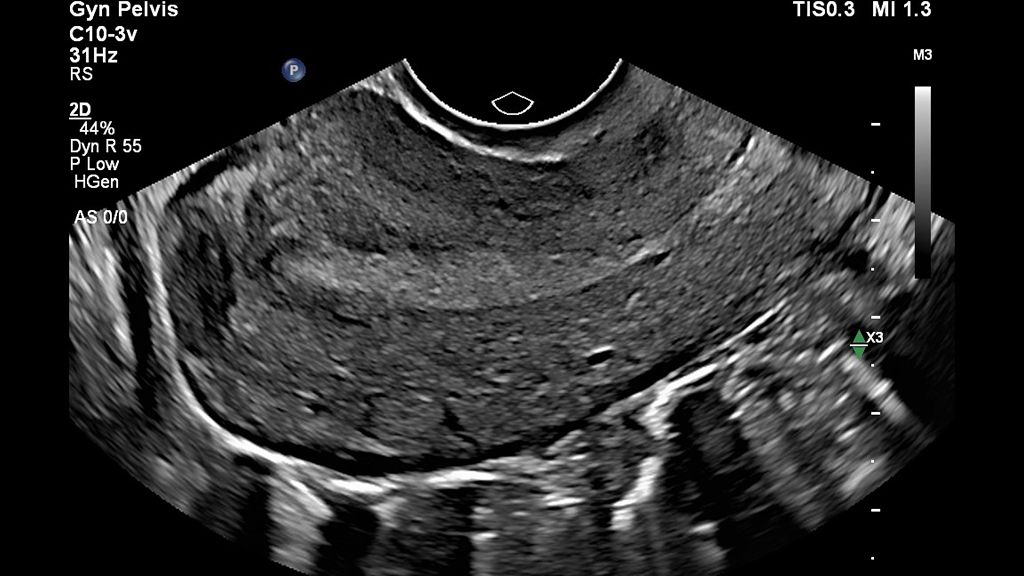

• Sagittal image of the uterus using a C10-3v transducer

Sagittal image of the uterus